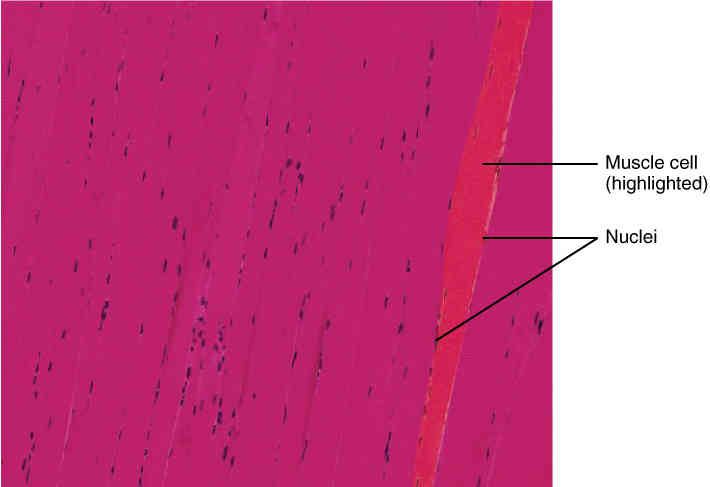

This page is under construction. For now, it is just a resource of the images found in the OpenStax Anatomy and Physiology Handbook. It wil slowly change into a revision tool. Each slide has a number. Use this to refer to the slide. When completed, it will have an unlabelled section, with labelled slides in parallel. On the unlabelled slides, write your answer and use the labelled slide to assess yourself. Keep track by also noting the number on each slide. Improvement at each attempt is important, more so than full marks on a first attempt.